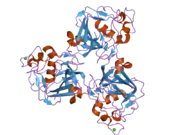

Ficolin-1, and also commonly termed M-ficolin is a protein that in humans is encoded by the FCN1 gene.[5][6][7]

Proteins of the ficolin family consist of a leader peptide, a short N-terminal segment, followed by a collagen-like domain, and a C-terminal fibrinogen-like domain. The name of ficolin was derived from the latter two domains. The collagen-like and the fibrinogen-like domains are also found in other proteins such as tenascins, while the former is also found in complement protein C1q and collectins, which include mannose-binding lectin and lung surfactant proteins. Ficolins selectively recognize acetylated compounds. M-ficolin encoded by FCN1 is predominantly expressed in the peripheral blood leukocytes, and has been postulated to function as a plasma protein with elastin-binding activity. Several SNPs have been described in the FCN1 gene with impact on serum concentrations of M-ficolin and the ligand binding ability. M-ficolin levels reflect disease activity and predict remission in early rheumatoid arthritis.